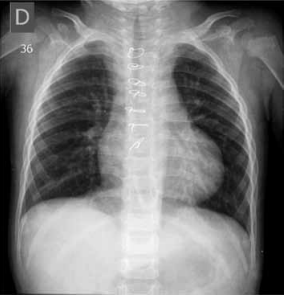

Paciente de 1 ano e 11 meses deu entrada no Pronto-

-Socorro com história de ânsia de vômito, palidez, sudorese e cianose ontem, sem perda de consciência. Hoje,

refere novo quadro de cianose e palidez com saturação

de 65% em ar ambiente, segundo aferição com o aparelho da mãe. Na avaliação atual, a saturação periférica da

criança em ar ambiente foi de 95%. Mãe refere que, com

3 dias de vida, teve diagnóstico de cardiopatia congênita

e bloqueio atrioventricular total, necessitando de implante de marca-passo definitivo, além de quadro convulsivo

(segue com neurologista), mas nunca havia ficado roxa

antes. Qual é a cardiopatia congênita provável associada

ao bloqueio atrioventricular? Considere a radiografia de

tórax atual a seguir.

(Arquivo pessoal; imagens usadas com autorização)